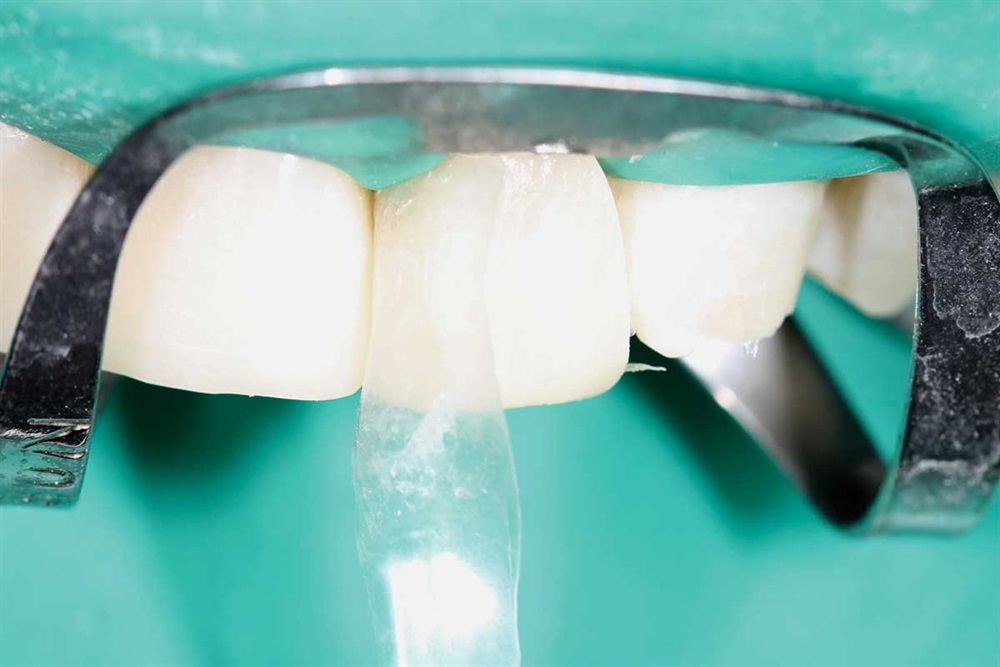

Fig. 8: First tooth done, but not finished. I built up the incisors about 5mm.

Fig. 11: Got the teeth all hitting with the same pressure. However, I kept the lower central incisors in lighter occlusion because they were worn more than the rest.